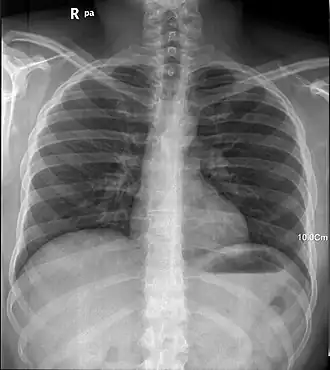

Röntgenstraling heeft belangrijke toepassingen in de geneeskunde, waarbij het medische nut voor de patiënt meestal ruimschoots opweegt tegen het geringe risico van stralingsschade. Beeldvorming ontstaat doordat de straling afhankelijk van de energie door de meeste zachte weefsels wordt doorgelaten, maar door vooral harder calciumhoudend weefsel wordt tegengehouden. Zo houdt bijvoorbeeld bot veel straling tegen maar kraakbeen veel minder tot geen. Sinds meer dan een eeuw kan daarom het skelet makkelijk met röntgenstraling worden afgebeeld.

Toepassingen in de geneeskunde zijn:

- als medische beeldvormende techniek voor diagnose (zie röntgenfoto, CT-scan en röntgendoorlichting, fluoroscopie) en